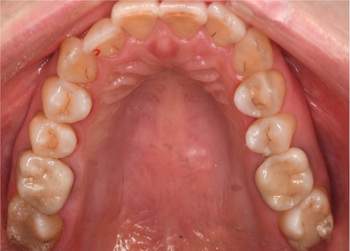

治療前

治療後